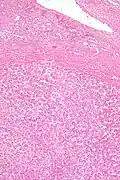

Hepatic adenomas are, typically, well-circumscribed nodules that consist of sheets of hepatocytes with a bubbly vacuolated cytoplasm. The hepatocytes are on a regular reticulin scaffold and less or equal to three cell thick.

The histologic diagnosis of hepatic adenomas can be aided by reticulin staining. In hepatic adenomas, the reticulin scaffold is preserved and hepatocytes do not form layers of four or more hepatocytes, as is seen in hepatocellular carcinoma.

Cells resemble normal hepatocytes and are traversed by blood vessels but lack portal tracts or central veins.

Micrograph of hepatic adenoma. H&E stain

Micrograph of hepatic adenoma. H&E stain -